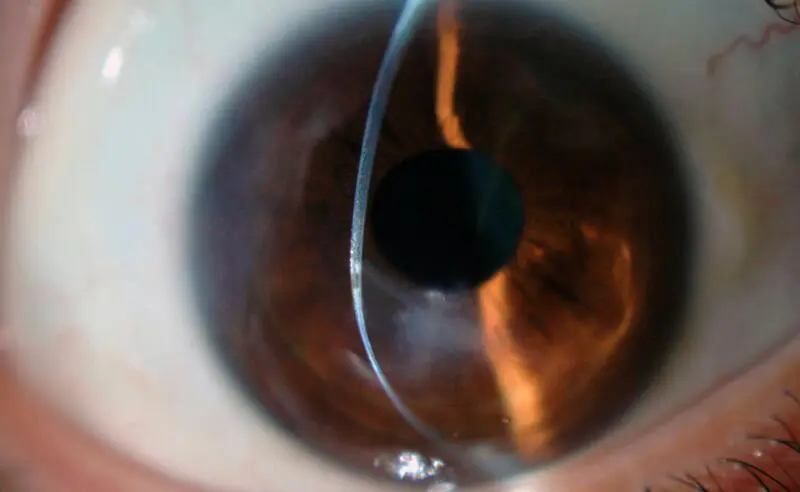

El queratocono se asocia a una deformación en forma de cono y su impacto es mayor en la cuenca mediterránea por su clima templado y floración frecuente y abundante, y su evolución empeora en áreas cálidas debido al frotamiento de los ojos causado por alergias, cuya frecuencia también es mayor en el mar Mediterráneo.

De hecho, han logrado un diagnóstico de la enfermedad basado en el desarrollo de la visión del paciente y su evolución morforvolumétrica y óptica de la deformación corneal.